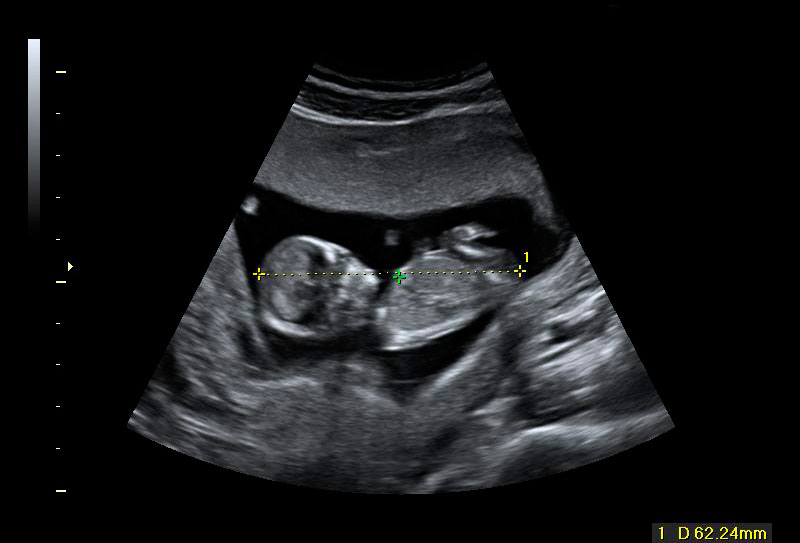

Dos de los fetos son gemelos

La imagen de esta ecografía en 4D de este embarazo muestra tres fetos, uno de ellos independiente, que está "aislado" de sus dos hermanos gemelos.

La ecografía en 4D no deja lugar a dudas: se trata de tres fetos, uno de ellos independiente (en la parte superior de la imágen), que está separado de sus hermanos gemelos por una membrana más gruesa. El embarazo gemelar está compuesto por dos fetos y dos bolsas, separadas por una fina membrana que apenas se aprecia en el vídeo. Los movimientos ecográficos nos permiten ver a las criaturas en diferentes planos.